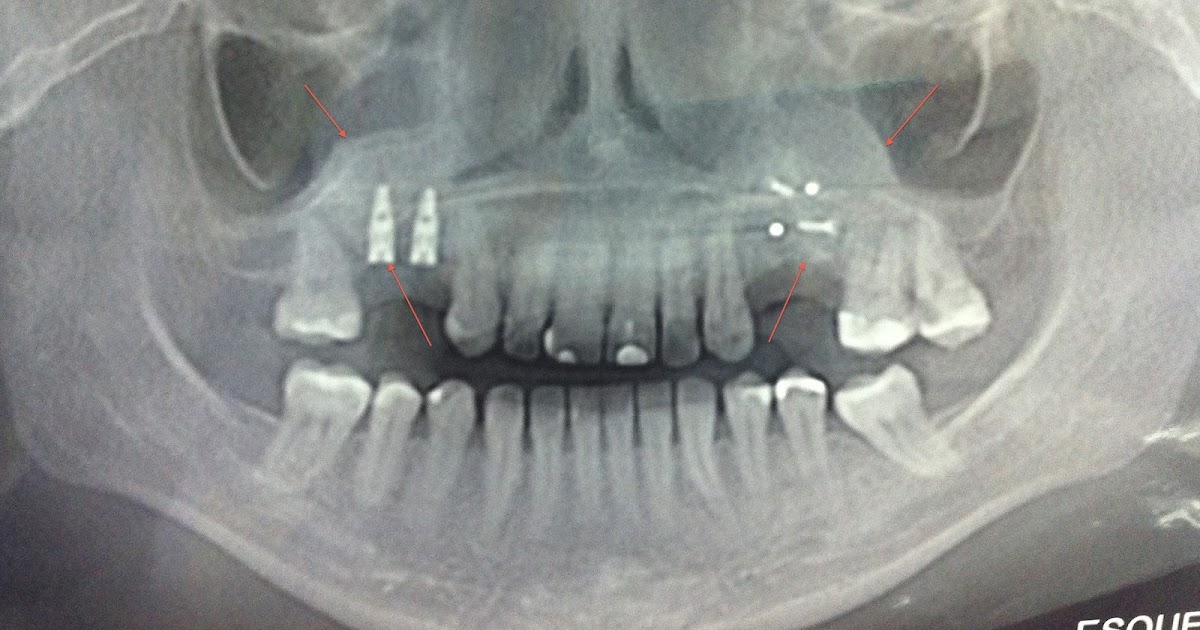

Levantamento Do Seio Maxilar

Resultado da ← voltar aos detalhes do artigo análise do levantamento de seio maxilar, pela técnica da janela lateral, para colocação de implantes dentários Resultado da o que é levantamento de seio maxilar? Para explicar rapidamente o que é o levantamento de seio maxilar, é um pequeno. Resultado da um dos meios de viabilizar osso para posterior fixação de implante dentário, na parte posterior da maxila superior, é através da técnica de. Resultado da o levantamento do seio maxilar, também conhecido como enxerto ósseo para a elevação do assoalho do seio maxilar ou. Resultado da levantamento do assoalho do seio maxilar, implantes dentários, cirurgia bucal. A perda de dentes não tratada é um sério problema de. Resultado da são paulo. Técnica traumática e atraumática de levantamento do. O levantamento de seio maxilar atraumático sem enxerto ósseo é eficaz para reabilitação de áreas edêntulas e mostra um.

Resultado da levantamento de seio maxilar: Uma comparação de técnicas. Journal of research in dentistry 6 (2):43. Resultado da o levantamento do seio maxilar, ou vulgarmente denominado sinus lift, é uma técnica cirúrgica aceite, simples, comum e. Resultado da o que é o levantamento do seio maxilar. O seio maxilar é uma cavidade em nossa face que tem diversas funções, muitas associada a respiração. Ana paula farnezzi bassi. O levantamento do assoalho do seio maxilar é um recurso muito utilizado. Resultado da © 2024 google llc. A elevação do seio ou aumento do seio maxilar é um procedimento de cirurgia oral em que um enxerto ósseo é colocado no.

Resultado da o que é o levantamento do seio maxilar ? O enxerto no seio maxilar é um procedimento seguro quando feito com os cuidados necessários. Resultado da levantamento do seio maxilar pela técnica da janela lateral uma revisão da. Lifting the maxillary sinus using the side window technique a. Resultado da o levantamento do seio maxilar é um procedimento cirúrgico que visa a correção de problemas estruturais do rosto.